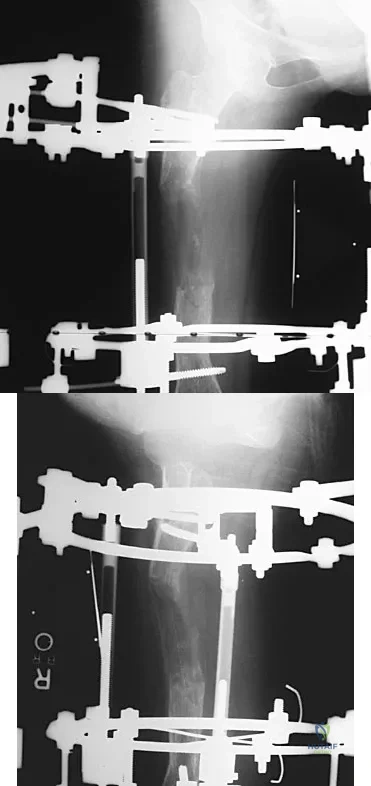

Question 24

Figures 45a and 45b show the AP and lateral radiographs of a 15-year old patient who is undergoing surgery to add 3 cm of length to the femur. Based on the radiographic findings, what is the next most appropriate step in management?

Explanation